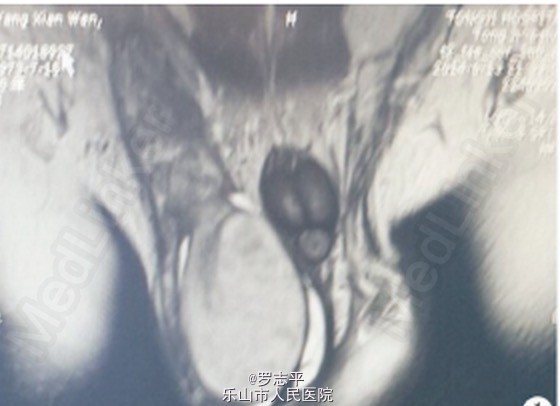

查体:右侧睾丸明显肿大,沉重感,触之质硬,无压痛,右侧精索明显增粗 MRI示:右侧睾丸及附睾异常信号增大,右侧睾丸大小58 mm×44 mm,T1 WI 信号大致均匀,T2 WI 信号稍欠均匀,呈散在点状稍低信号改变,DWI扫描信号均匀,右侧附睾精索明显增粗并呈显著不均匀强化改变,考虑肿瘤